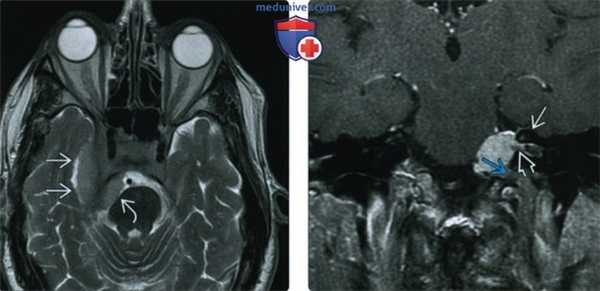

(Слева) При MPT Т2 ВИ в аксиальной проекции у этого же пациента определяется менингиома среднего отдела основания черепа; опухоль примерно изоинтенсивна по сравнению с серым веществом, между опухолью и смещенной височной долей видна ликворная/сосудистая щель. Небольшой компонент опухоли в задней черепной ямке деформирует мост.

(Справа) При корональной МРТ Т1 ВИ FS с КУ на медиальной поверхности пирамиды височной кости определяется экстрааксиальное объемное образование, прорастающее во внутренний слуховой проход и яремное отверстие. Виден гиперостоз верхней стенки внутреннего слухового прохода.